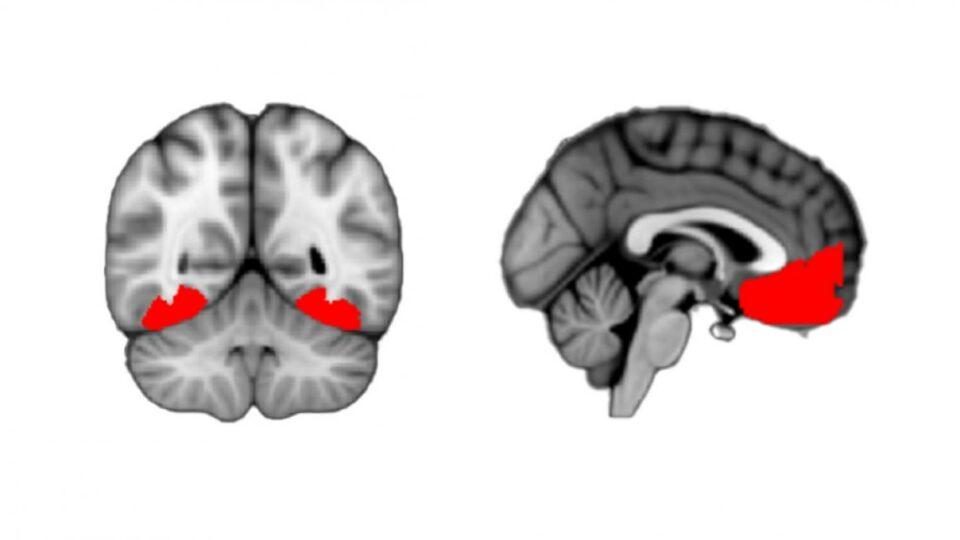

Estas calificaciones se cruzaron con los escáneres fMRI, y se observó actividad notable en tres regiones: la corteza occipitotemporal (vinculada a la visión y reconocimiento de objetos), la corteza prefrontal ventromedial o vmPFC (que maneja percepciones de valor y confianza) y la corteza cingulada anterior (utilizada para la recolección de información).

La vmPFC parece actuar como un puente neurológico entre los niveles de certeza registrados por la corteza occipitotemporal y las sensaciones subjetivas de curiosidad, casi como un disparador que nos indica cuándo ser curiosos. Cuanto menos confiaban los voluntarios en identificar el sujeto de la imagen, más curiosidad sentían al respecto.